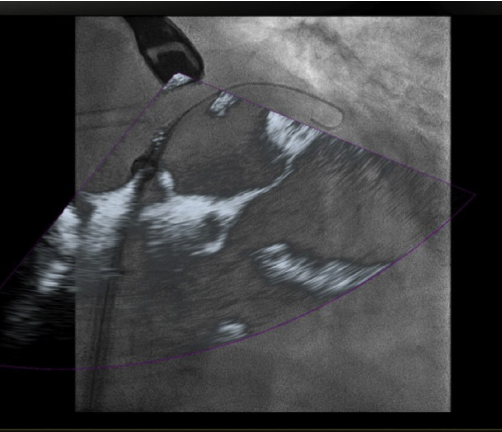

Figura 1 Imagen de fusión eco 3D/fluoroscopia. Se observa paso de la guía a través de la válvula aórtica, alojándose en el ventrículo izquierdo durante procedimiento de TAVI.

En respuesta a las necesidades de buenos resultados y seguridad para el paciente durante la realización de procedimientos complejos, se desarrolló un software capaz de fusionar la fluoroscopia y la ecocardiografía transesofágica 2D/3D13 en una sola imagen (figs. 2 y 3). Viene utilizándose cada vez con más frecuencia, con múltiples reportes en la literatura, pues ha mostrado sus buenos resultados de eficacia y especialmente de seguridad, dando la posibilidad de su implementación en la rutina diaria.